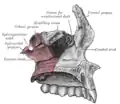

Vista inferior, com dentes. Superfície lateral.

Superfície lateral. Interior da superfície lateral.